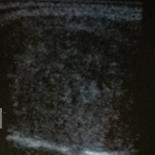

图2 甲状腺良性结节消融前横切位 30×22×20mm